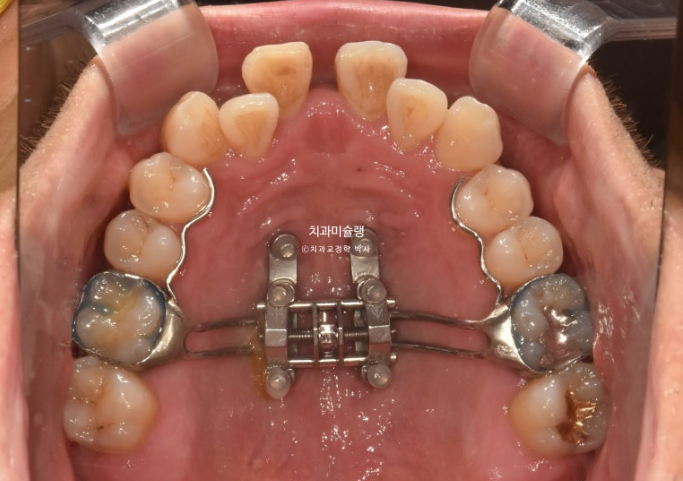

24년 10월 악궁확장이 성공하여 앞니 사이가 벌어졌습니다.

24.10

이렇게 앞니가 벌어지면 잘된 일입니다.

악궁확장 장치는 약 6개월간 유지하여 벌어진 봉합부에 다시 단단한 뼈가 차오르도록 도모합니다.